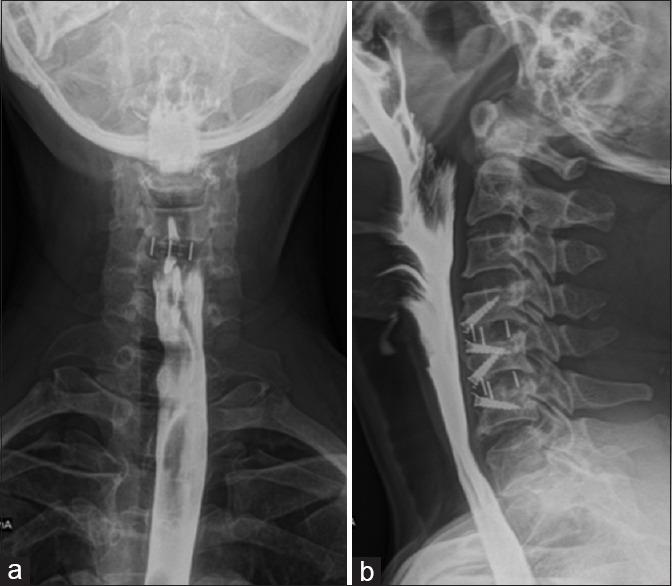

Cervical osteophytes may be seen in diffuse idiopathic skeletal hyperostosis, ankylosing spondylitis, posttraumatic, postoperative, degenerative causes, cervical spondylosis, and infectious spondylitis. A cervical osteophyte is very rarely considered among the differentials for symptoms of dysphagia. C5-C6 as well as C6-C7 being a site of greater load-bearing and mobility, the propensity to form osteophytes is high, with a small osteophyte leading to local mass effect. A 42-year-old male patient presented with mild dyspnea and significant dysphagia since 8 months, accompanied by dysphonia, weight loss, and intermittent aspiration. Clinical examination including neurological examination was normal. A barium swallow showed that osteophytes were severely protruding and displacing the lower pharynx and the proximal esophagus anterosuperiorly. The patient underwent surgical removal of the osteophyte through Smith-Robinson approach. Complaints of dysphagia were significantly decreased in postoperative period. A thorough evaluation is necessary to rule out other causes of dysphagia. Surgical management of this uncommon condition might be considered after confirmation of the osteophyte to be the offending lesion as it has favorable clinical outcomes.

颈椎骨赘可见于弥漫性特发性骨肥厚、强直性脊柱炎、创伤后、术后、退行性病因、颈椎病和感染性脊柱炎。在吞咽困难症状的鉴别诊断中,颈椎骨赘很少被考虑。C5-C6以及C6-C7是负重和活动度较大的部位,形成骨赘的倾向较高,小的骨赘会导致局部肿块效应。一名42岁男性患者自8个月以来出现轻度呼吸困难和明显的吞咽困难,伴有声音嘶哑、体重减轻和间歇性误吸。包括神经系统检查在内的临床检查均正常。吞钡检查显示骨赘严重突出并将下咽和食管近端向前上方推移。患者通过Smith-Robinson入路接受了骨赘切除术。术后吞咽困难的主诉明显减轻。有必要进行全面评估以排除吞咽困难的其他原因。在确认骨赘为致病病变后,可考虑对这种罕见情况进行手术治疗,因为其临床效果良好。